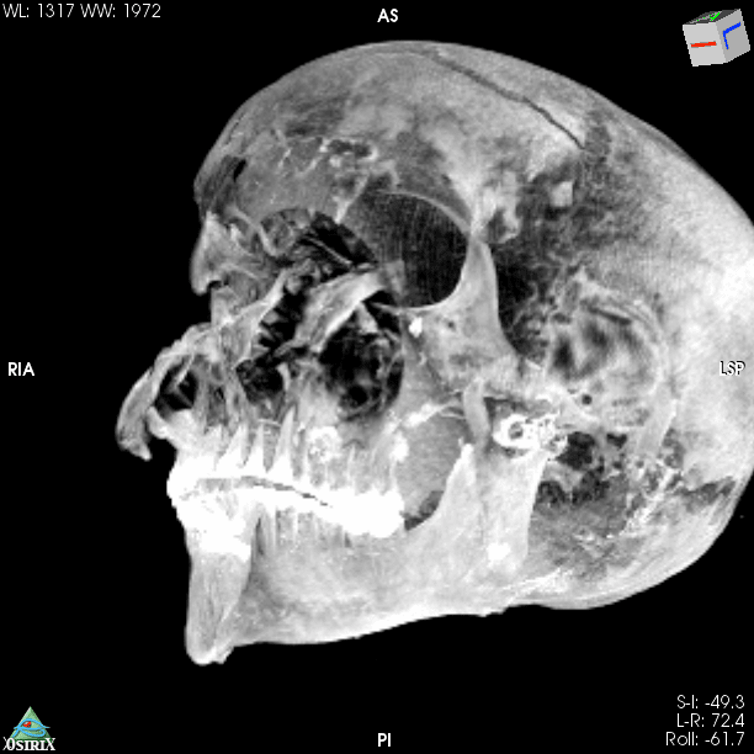

جرح بجبهته، وقطع فوق عينه اليمنى، وكسر في الأنف وعظام الوجنة، وقطع بمنطقة الخد الأيسر، وكسور فوق أذنه اليمنى، وكسر في عظم جمجمته يمتد خلف العينين. كشف تقرير نشره موقع ...